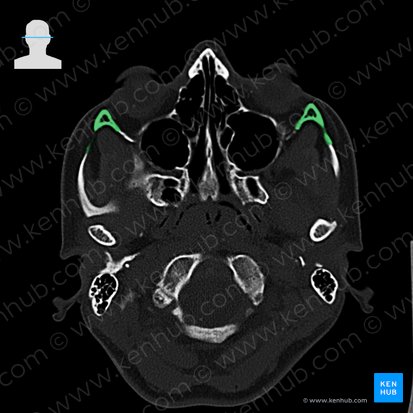

Os zygomaticum (Jochbein)

Das paarig vorliegende Os zygomaticum, auch Jochbein oder Wangenbein genannt, gehört zu den Knochen des Gesichtsschädels (Viscerocranium). Es liegt am lateralen Rand der Orbita und bildet deren seitliche Begrenzung. Dort verleiht es den Wangen ihre charakteristische Form.

Das Os zygomaticum lässt sich in verschiedene Bereiche unterteilen: einen Corpus (Körper), drei Processus (Fortsätze) und drei Facies (Oberflächen).

Die glatte Facies orbitalis bildet einen Großteil der lateralen und kaudalen Orbitawand und ist geringfügig an der Begrenzung der Fissura orbitalis inferior beteiligt. Die Grenze zur Facies lateralis wird als Margo infraorbitalis bezeichnet. Etwa mittig liegen das Foramen zygomaticoorbitale und der Canalis zygomaticoorbitalis, durch welchen die Nn. zygomaticofacialis et zygomaticotemporalis ins Os zygomaticum eintreten.